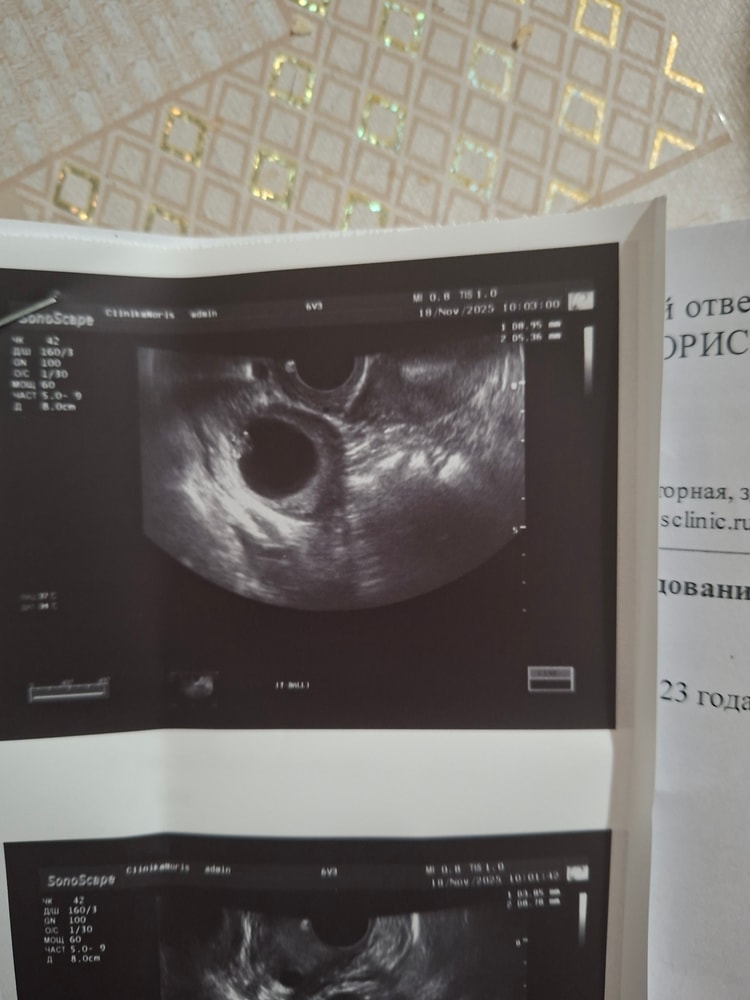

Выглядела так

ЕкатеринаБалерина, у меня был фаликул 19мм сделали укол хгч 5000ед

Через 5 дней сделала это узи и вот думаю это желтое тело после овуляции или это фаликул не лопнул

Киста желтого тела с хорошим кровотоком и в основном сетчатой структуры

При цдк кровоток +

Фолликулярная круглая, черная, кровоток отсутствует или минимален